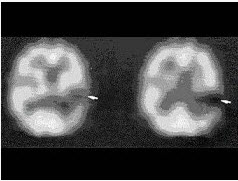

22、单项选择题

男性患者恶性脑肿瘤术后6年复查,有放疗病史,无明显症状,行MRI及99Tcm-ECD脑血流灌注显像,后者提示局部脑血流减低,行201Tl脑显像如图,诊断是()。

A.箭头示手术瘢痕形成

B.箭头示液化坏死区

C.箭头示肿瘤复发

D.箭头示肿瘤脑转移

E.以上都不是